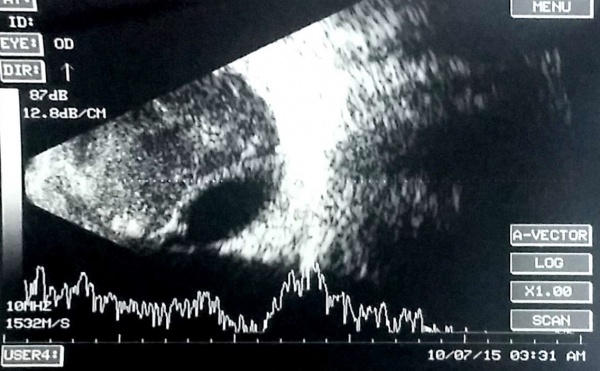

[The funnel RD is attached to the disc and is not showing after-movements with ocular movements.]